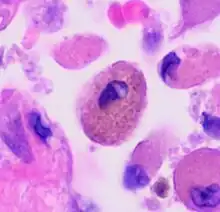

| Respiratory bronchiolitis | "Smoker’s macrophages" | Yellow to light brown and finely granular[4] | Airways (especially respiratory bronchioles) | Tobacco smoking | ![]() |

Smoker's macrophage in center |